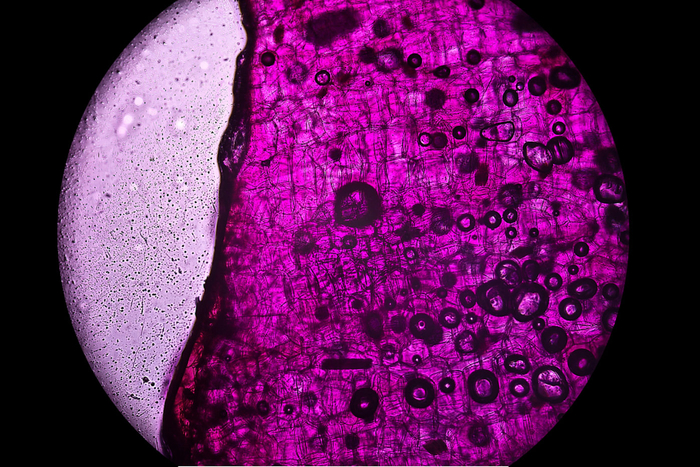

这一问题的根源,在于细胞治疗的“两面性”。对细胞治疗的最简单定义,是指从人体抽取机体细胞,在体外经过各种处理后,再回输人体的一种治疗方式。所谓“两面性”是指,前述治疗过程既可定义为诊疗行为,也即细胞的提取、处理及回输的诊疗行为,也可将在体外进行处理的细胞定义为一种特殊的生物药品。